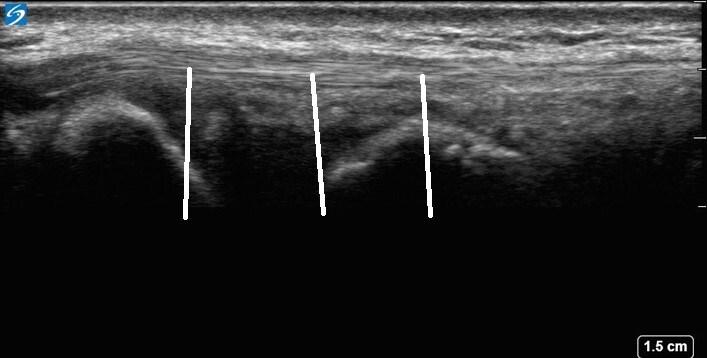

Wrist Compartment Five 2 Image

The lines point to the extensor digiti minimi